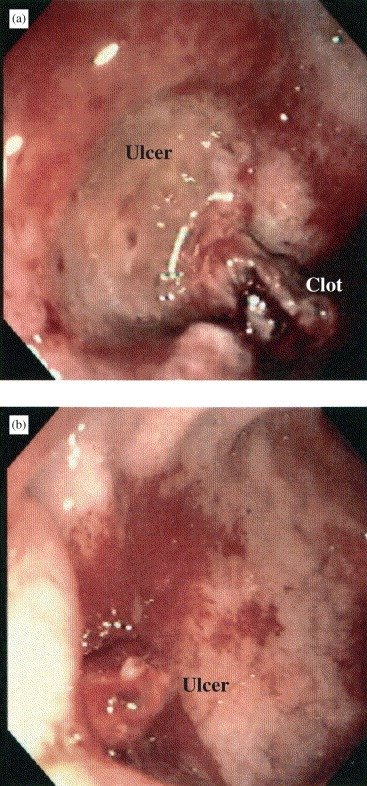

Imagem endoscópica de úlcera de estresse em paciente crítico em UTI. Aqui não se trata de ‘ácido em excesso’, mas de um desequilíbrio profundo entre fatores protetores e agressores da mucosa gastrointestinal, típico do estado crítico. Em alguns casos, como este, a lesão evolui para sangramento gastrointestinal clinicamente significativo, o verdadeiro desfecho que importa, e não a simples presença da úlcera.

Se você fizer uma endoscopia em pacientes críticos de UTI, 70% a 90% deles terão erosões ou úlceras superficiais da mucosa gástrica. Isso é quase regra, não exceção.

Mas aqui vem o ponto-chave que muda completamente a conduta: a imensa maioria dessas úlceras nunca vai sangrar de forma clinicamente relevante.

E se não vai sangrar, não muda desfecho. Não aumenta a mortalidade. Não exige intervenção. Muitas desaparecem espontaneamente à medida que o paciente melhora.

Portanto, o objetivo da profilaxia não é evitar a formação de úlcera, porque isso é praticamente inevitável em pacientes críticos. O objetivo real é prevenir sangramento gastrointestinal clinicamente significativo.